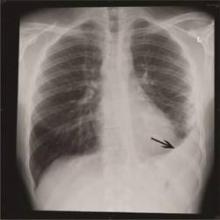

Among older adults, hospitalization for pneumonia raises the short-term (1-month) and long-term (10-year) risk of cardiovascular disease events to a degree comparable to those of smoking, diabetes, and hypertension, according to a report published online Jan. 20 in JAMA.

The 591 participants in the Cardiovascular Health Study were 65 years of age or older and had been hospitalized for pneumonia. When researchers compared their outcomes to 1,182 matched controls without pneumonia, they found that in the pneumonia group the rate of CVD events was fourfold higher at 30 days, dropped to twofold higher throughout the rest of the first year, and leveled out at 1.5-fold higher for the remainder of the decade.

Researchers then verified this risk pattern in a cohort of 680 pneumonia patients aged 45-64 years and 1,360 matched controls in the Atherosclerosis Risk in Communities study. The increased risk conferred by hospitalization for pneumonia persisted after the data were adjusted to account for demographic traits, preexisting CVD risk factors, and measures of patient frailty; it also was robust to numerous sensitivity analyses, the researchers said (JAMA 2015 Jan. 20 [doi:10.1001/jama.2014.18229]).